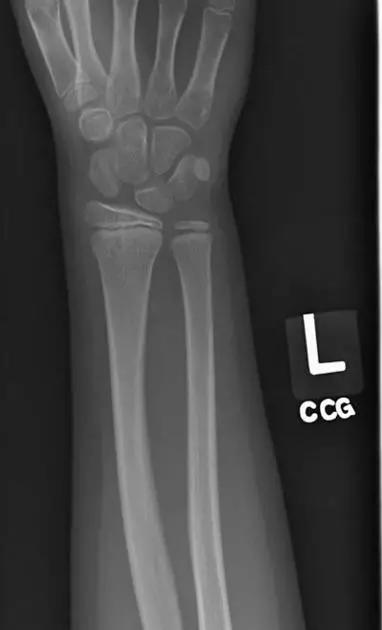

10. Galeazzi 骨折(盖氏骨折)

桡骨干下 1/3 骨折合并尺骨小头脱位。

盖氏骨折正侧位(来源:Orthobullets)